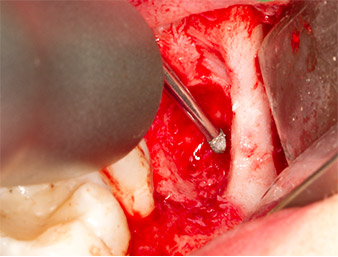

Das Gewebe über dem Wurzelrest war nicht vollständig verknöchert und bestand zu einem großen Teil aus entzündlich verändertem Granulationsgewebe (Abb. 4).

Granulationsgewebe

Abb. 4: Zwei Langenbeck-Haken und ein Raspatorium nach Prichard stellen das OP-Feld dar. Granulationsgewebe der unvollständig abgeheilten ersten Osteotomie ist zu erkennen.